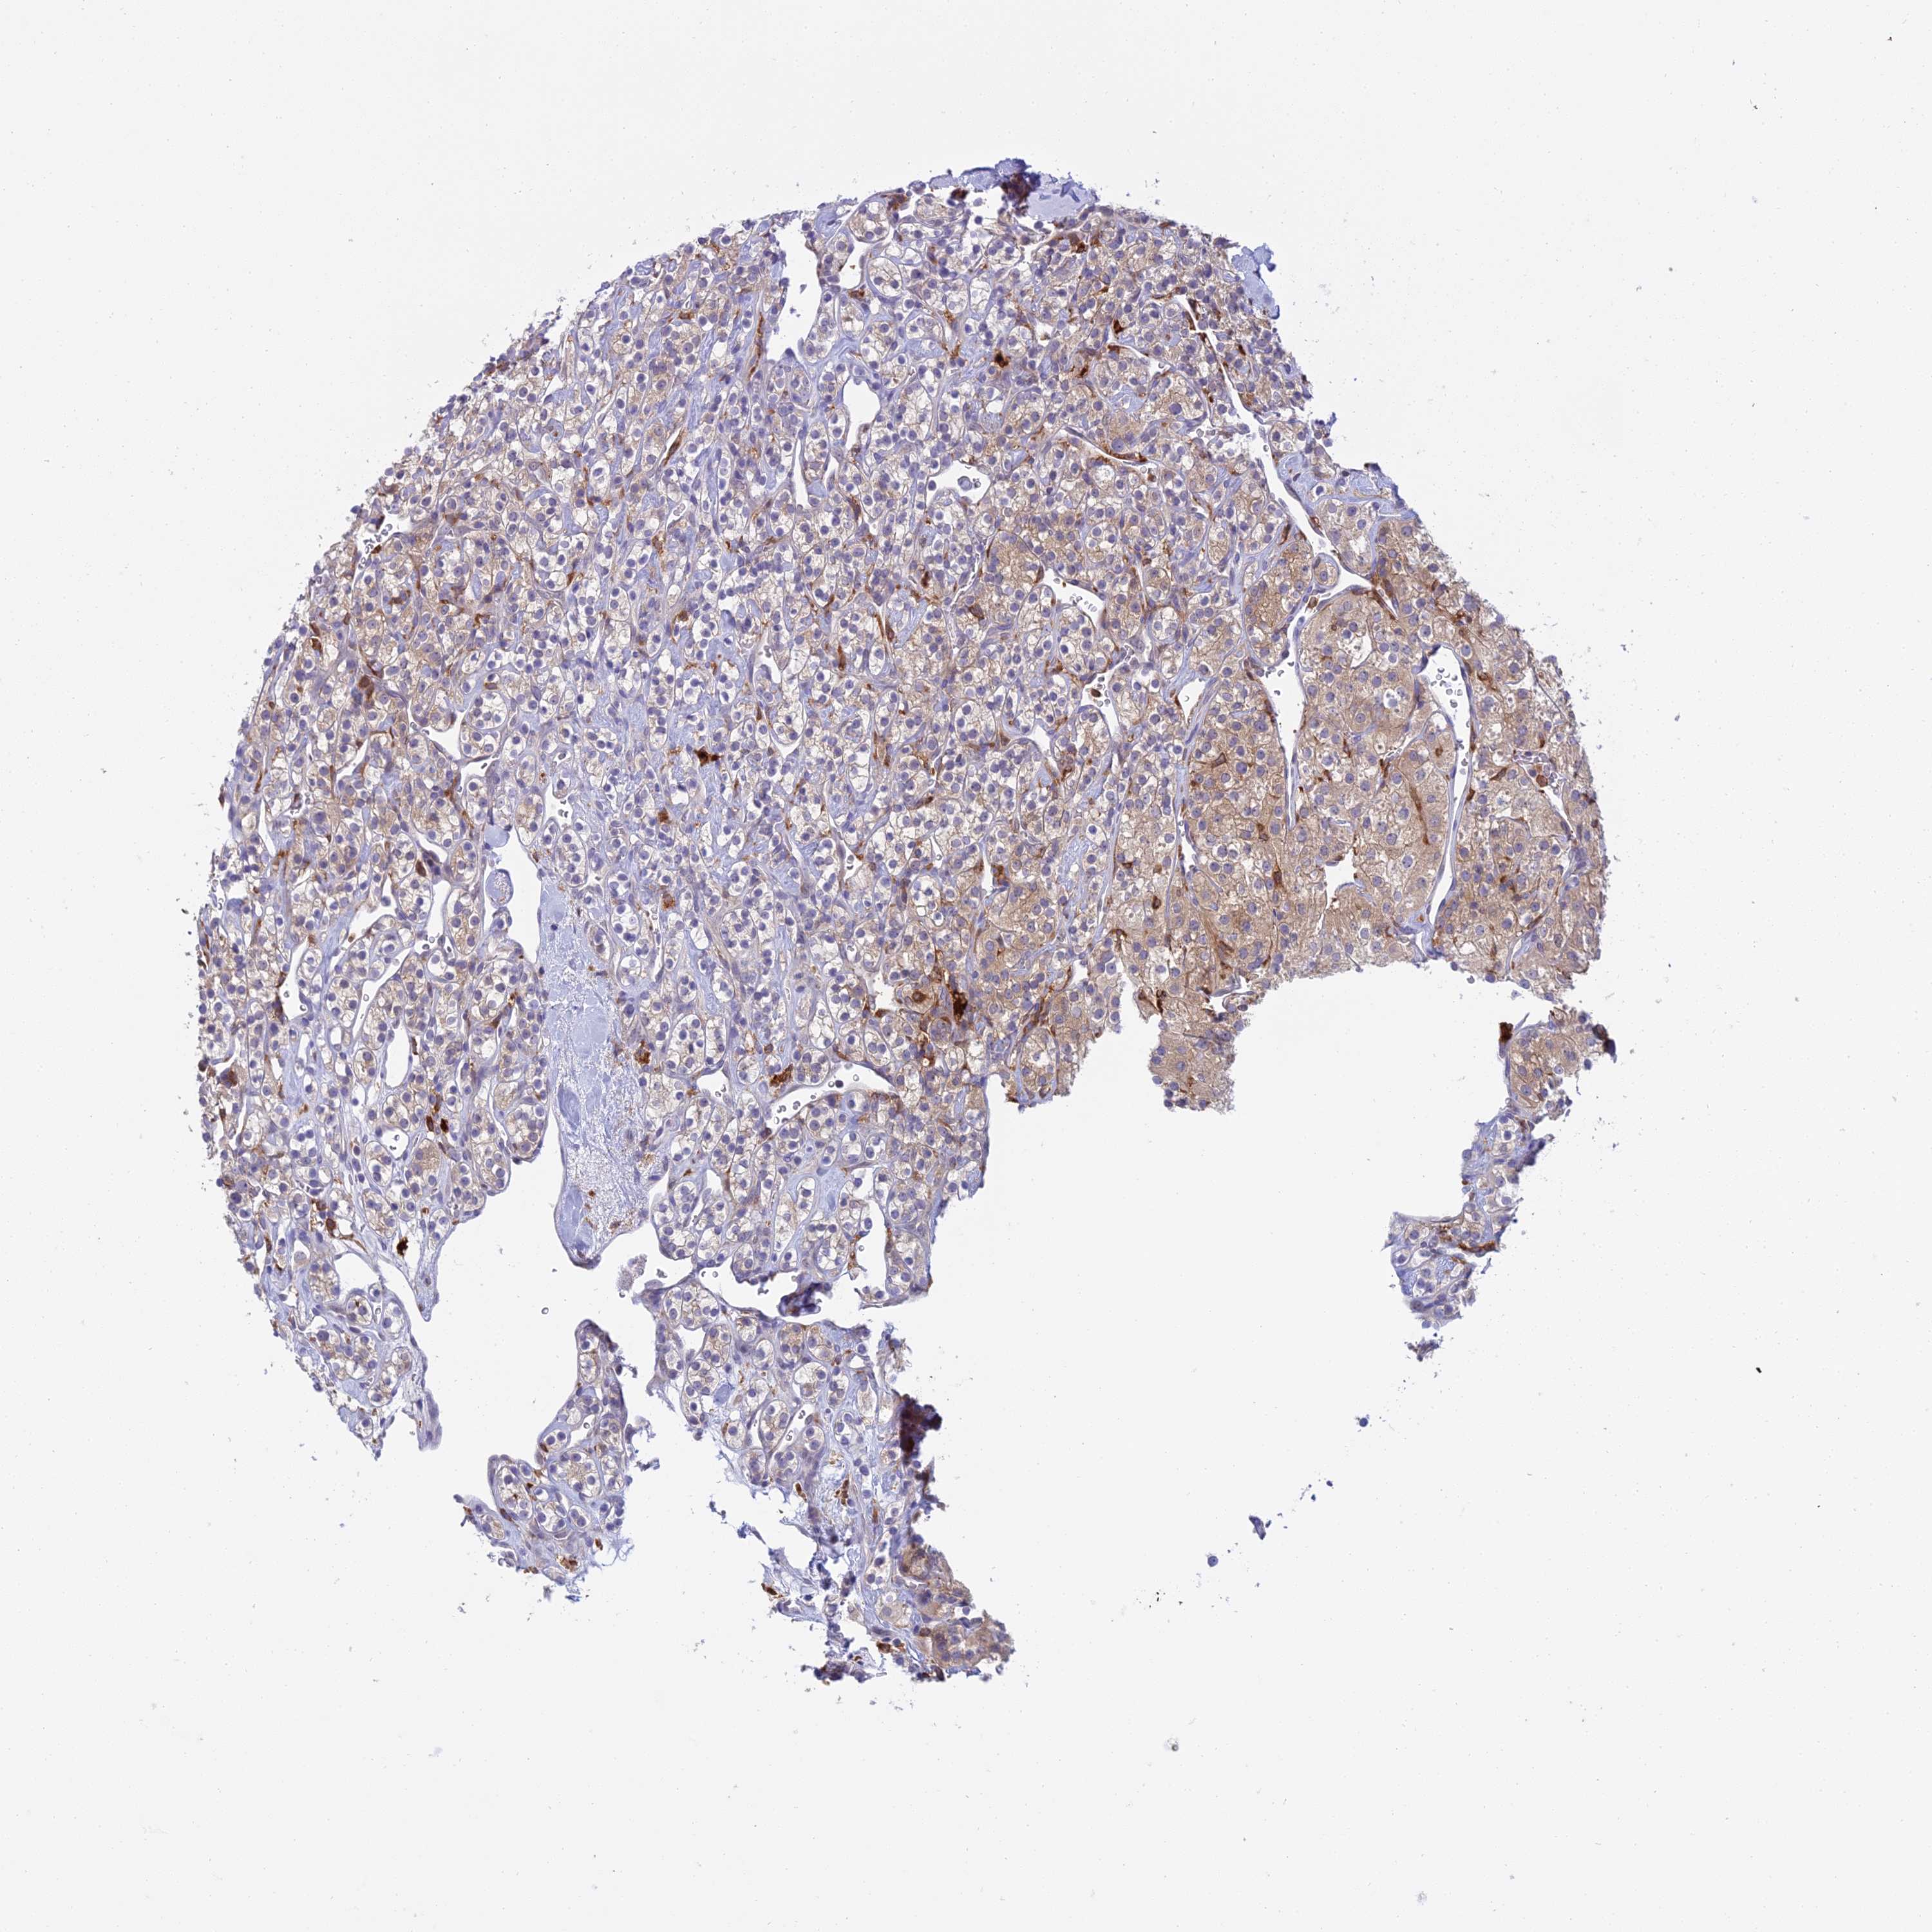

KIDNEY RENAL CLEAR CELL CARCINOMA (VALIDATION) - Interactive survival scatter ploti

The Survival Scatter plot shows the clinical status (i.e. dead or alive) for all individuals in the patient cohort, based on the same data that underlies the corresponding Kaplan-Meier plots. Patients that are alive at last time for follow-up are shown in blue and patients who have died during the study are shown in red.

The x-axis shows the expression levels (FPKM) of the investigated gene in the tumor tissue at the time of diagnosis. The y-axis shows the follow-up time after diagnosis (years). Both axes are complimented with kernel density curves demonstrating the data density over the axes. The top density plot shows the expression levels (FPKM) distribution among dead (red) and alive patients (blue). The right density plot shows the data density of the survived years of dead patients with high and low expression levels respectively, stratified using the cutoff indicated by the vertical dashed line through the Survival Scatter plot. This cutoff is automatically defined based on the FPKM cutoff that minimizes the p-score. The cutoff can be changed by dragging the vertical line or by entering a cutoff value in the square labeled "Current cut-off".

Under the Survival Scatter plot the p-score landscape (black curve; left axis) is shown together with dead median separation (red curve; right axis). Dead median separation is the difference in median mRNA expression between patients who have died with high and low expression, respectively. It is calculated as follows: median FPKM expression of dead patients with high expression - median FPKM expression of dead patients with low expression. This is intended to aid the user in visually exploring custom cutoffs and the associated p-scores and dead median separation.

Individual patient data is displayed and can be filtered by clicking on one or more of the category buttons on the top of the page. Categories describing expression level and patient information include: high, low, alive, dead, female, male and tumor stages. The scale of the x-axis can be toggled between linear and log-scale by clicking on the "x log" button. Mouse-over function shows TCGA ID, patient information and mRNA expression (FPKM) for each patient.

& Survival analysisi

Kaplan-Meier plots summarize results from analysis of correlation between mRNA expression level and patient survival. Patients were divided based on level of expression into one of the two groups "low" (under cut off) or "high" (over cut off). X-axis shows time for survival (years) and y-axis shows the probability of survival, where 1.0 corresponds to 100 percent.

UBE2G1 is not prognostic in Kidney Renal Clear Cell Carcinoma (validation)

Best expression cut offi

Based on the FPKM value of each gene, patients were classified into two groups and association between prognosis (survival) and gene expression (FPKM) was examined. The best expression cut-off refers the FPKM value that yields maximal difference with regard to survival between the two groups at the lowest log-rank P-value. Best expression cut-off was selected based on survival analysis .

When clicking on this number, the vertical dashed line indicating cut-off, the interactive survival plot, and the Kaplan-Meier curve will be adjusted to show results based on the best expression cut-off.

: 26.08

P scorei

Log-rank P value for Kaplan-Meier plot showing results from analysis of correlation between mRNA expression level and patient survival.

N/A

5-year survival highi

5-year survival for patients with higher expression than the expression cutoff.

For melanoma and glioma, 3-year survival is shown.

5-year survival lowi

5-year survival for patients with lower expression than the expression cutoff.

TCGA RNA samplesi

RNA-seq data is reported as average FPKM (number Fragments Per Kilobase of exon per Million reads), generated by the The Cancer Genome Atlas (TCGA) .

Normal distribution across the dataset is visualized with box plots, shown as median and 25th and 75th percentiles. Points are displayed as outliers if they are above or below 1.5 times the interquartile range. FPKM values of the individual samples are presented next to the box plot.

Average pTPM 25.8

Number of samples 100